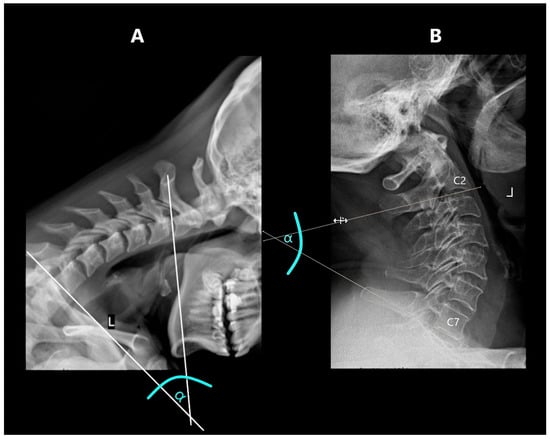

2.7. Range of Angular Motion (ROM)

The range of angular motion was measured in the flexion and extension projections. The measurement was performed by determining the tangent to the lower contour of the upper vertebra and a second tangent drawn to the upper contour of the lower vertebra (Figure 3). The sum of the angles obtained in flexion and extension at a specific level was defined as its segmental angular mobility.

This study also determined the overall ROM of the C2–C7 cervical spine by summing the segmental angular mobility values for each level.

Figure 3. Measuring ROM: (A)—in extension, (B)—in flexion.